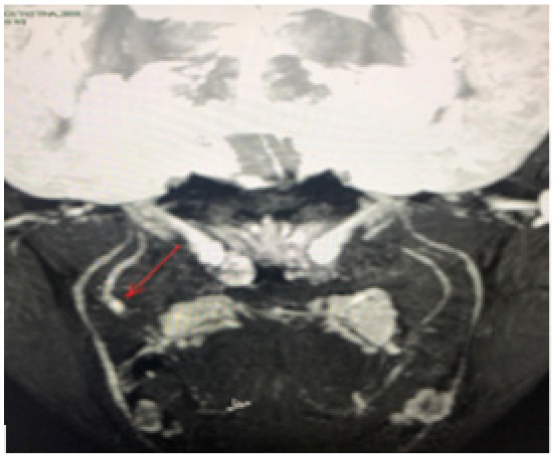

Patient underwent a magnetic resonance neurography of the lingual nerve, which showed a neuroma on the right LN and a section area (Figure 1). Based on the patient’s medical history, a potential microsurgical repair of the LN was offered, with aiming successful restoration of neurosensory function.